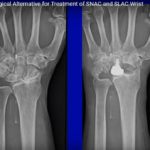

Four Corner Arthrodesis for SNAC wrist using a variable angle locking plate

Courtesy: Dr Dominic Power, FRCS, Consultant Hand Surgeon, Birmingham Hand Centre, UK

• Motion preserving alternatives for SNAC and SLAC Wrist

Courtesy: Arthrosurface and Randall Culp MD, Philadelphia Hand to Shoulder Center 672 S. River Street,…